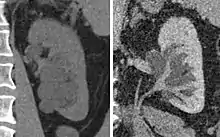

Hydronephrosis due to a kidney stone at the ureteral vesicular junction seen on CT scan

Prenatal diagnosis is possible,[7] and in fact, most cases in pediatric patients are incidentally detected by routine screening ultrasounds obtained during pregnancy.[8] However, approximately half of all prenatally identified hydronephrosis is transient, and resolves by the time the infant is born, and in another 15%, the hydronephrosis persists but is not associated with urinary tract obstruction (so-called non-refluxing, non-obstructive hydronephrosis). For these children, regression of the hydronephrosis occurs spontaneously, usually by age 3. However, in the remaining 35% of cases of prenatal hydronephrosis, a pathological condition can be identified postnatally.[9]

The choice of imaging depends on the clinical presentation (history, symptoms and examination findings). In the case of renal colic (one sided loin pain usually accompanied by a trace of blood in the urine) the initial investigation is usually a spiral or helical CT scan. This has the advantage of showing whether there is any obstruction of flow of urine causing hydronephrosis as well as demonstrating the function of the other kidney. Many stones are not visible on plain X-ray or IVU but 99% of stones are visible on CT and therefore CT is becoming a common choice of initial investigation. CT is not used, however, when there is a reason to avoid radiation exposure, e.g. in pregnancy.[11][12]